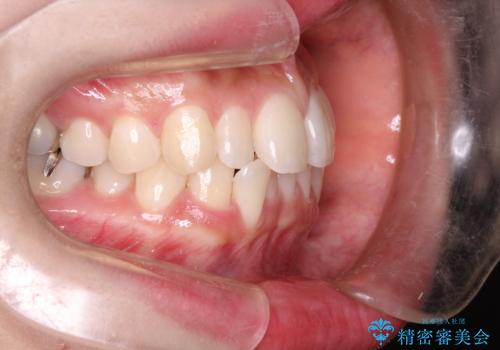

初診時の歯並びの状態としては、上下ともに前歯部の中等度のがたつきがあり、特に左上の前歯が1本内側に入り込んでしまっている状態でした。

内側に入り込んでしまっている歯を出してくることに非常に時間がかかりましたが、一度歯を歯茎の方へ押し込みそして前へ出してくる2段階の治療を行いました。